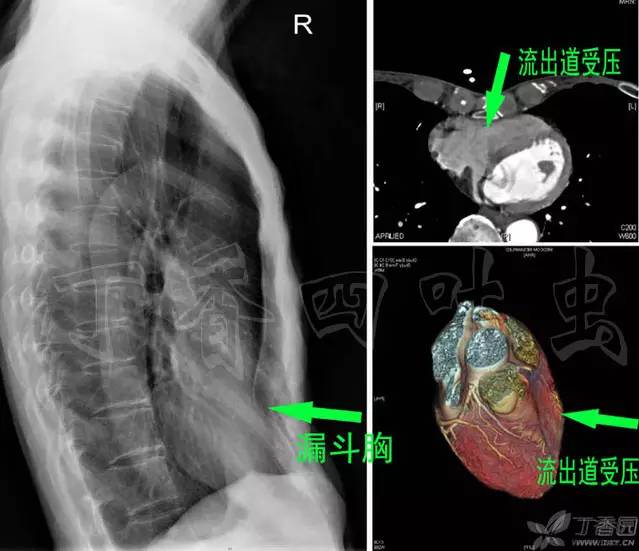

有了正确的心脏观,我们就知道如果一个人是漏斗胸,它很可能压迫到右心室流出道,而不会压迫到左心室,如图。